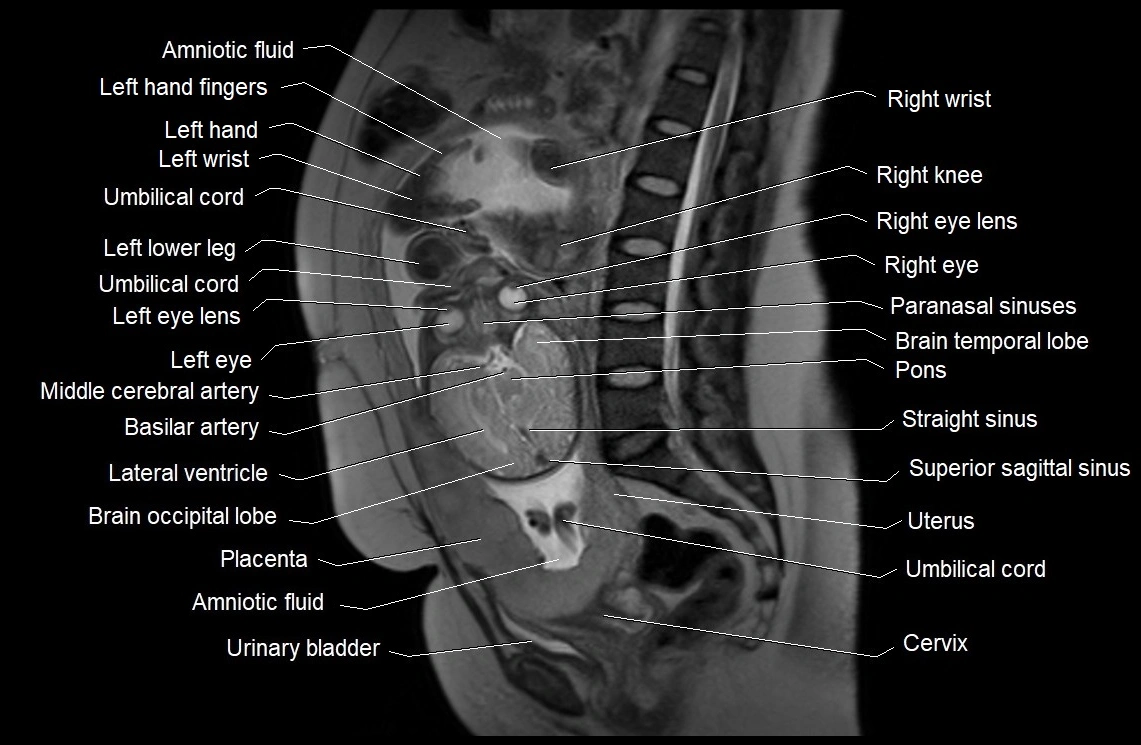

MRI Appearance

T2 HASTE (T2 GRE):

• Amniotic fluid shows very bright hyperintense signal

• Provides natural contrast against fetus and placenta

• Small particles (vernix) may appear as scattered hypointense foci within bright fluid

MRI image

image